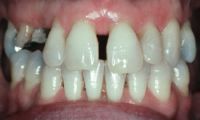

La queja principal de este paciente era la incomodidad durante el funcionamiento de los dientes anteriores inferiores. Nótese la pérdida y recesión de encía. Todos los incisivos tenían grado 2 de movilidad.

Otro factor que complicaba el caso fue que el paciente había completado dos años de tratamiento de ortodoncia para cerrar el espacio que existía en anteriores debido a la pérdida de un incisivo central por enfermedad periodontal. Hay evidencia radiográfica de pérdida de masa ósea de más del 70% en el incisivo central restante.